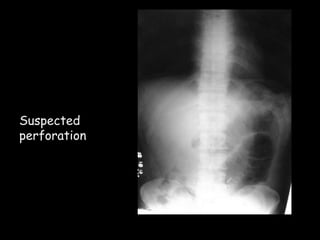

Plain radiographs

Initial investigation in casualty

Suspected

perforation

Obstruction